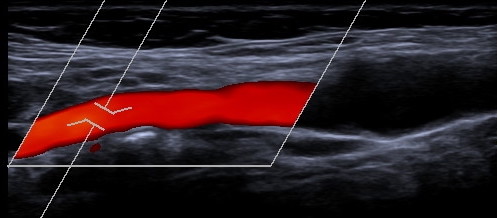

Gefäßdarstellung mittels Ultraschall

Bei der Doppler-Duplex-Sonographie der Halsgefäße wird untersucht, ob Verkalkungen (Plaques) vorliegen, und ob es dadurch zu Verengungen (Stenosen) kommt.

Neben dem Aussehen der Plaques wird die lokale Flussgeschwindigkeit des Blutes beurteilt: Je schneller die Flussgeschwindigkeit, desto hochgradiger die Stenose.